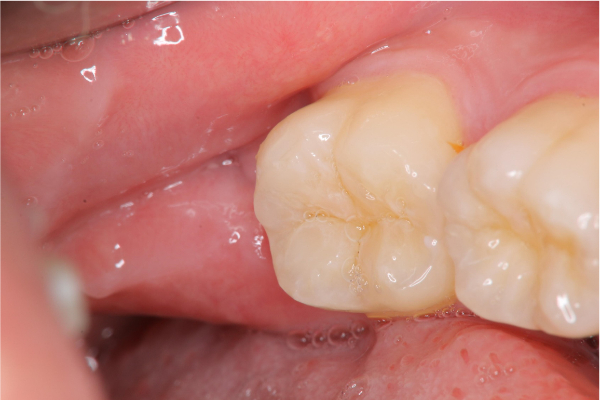

1週後傷口癒合良好